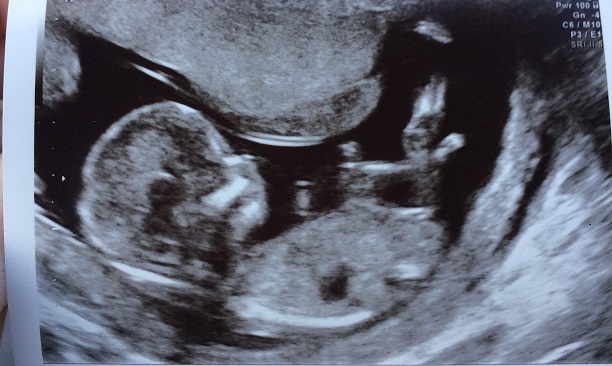

I would love some guesses on my baby's nub! By my dates I'm 13+3 but baby measured 14+2 at my dating scan today. Baby had its bum slightly angled away, so I'm not confident in my own guess and would love some impartial eyes to have a look and give me their opinions!

Attachment 34619

I would wait a bit before buying anything, but I can say that NONE of my boys' scans looked like that! If I saw that during a scan at this gestation, I would be cautiously excited! All of my boys had a visible scrotum and penis from 13w-13w5d.

I would be surprised if this ended up being a boy [emoji6]!